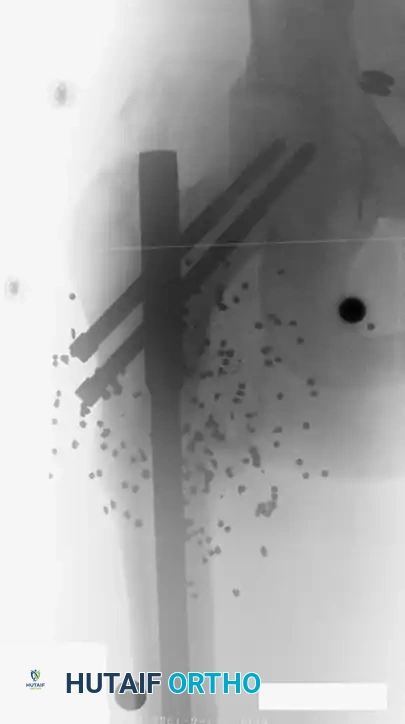

إصابات الأسلحة النارية والطلقات الباليستية

تمثل إصابات الطلق الناري تحدياً خاصاً في جراحة العظام، وتختلف طرق التعامل معها بناءً على سرعة وحجم المقذوف.

الإصابات الناتجة عن الأسلحة النارية منخفضة السرعة مثل المسدسات العادية غالباً ما تسبب ضرراً محدوداً للأنسجة الرخوة، ويمكن إدارتها في كثير من الأحيان من خلال العناية الموضعية بالجرح وبروتوكولات تثبيت الكسور القياسية.

على النقيض من ذلك، فإن الأسلحة النارية عالية السرعة مثل البنادق تنقل طاقة حركية هائلة إلى الجسم. هذه الطاقة تخلق موجة تصادمية وتجويفاً مؤقتاً يدمر الأنسجة والعضلات والأوعية الدموية في مناطق تتجاوز بكثير مسار الرصاصة الفعلي. هذه الحالات تتطلب استكشافاً جراحياً واسعاً وتنظيفاً جذرياً.

أما إصابات البنادق التي تطلق شظايا متعددة عن قرب، فتسبب دماراً كارثياً للأنسجة والعظام. يحذر الأطباء من محاولة إزالة كل شظية معدنية صغيرة متناثرة في العضلات، لأن محاولة استخراجها قد تسبب ضرراً جراحياً أكبر من الضرر الذي تسببه الشظايا نفسها. ومع ذلك، فإن أي شظايا تستقر داخل المفاصل يجب إزالتها فوراً لمنع تآكل المفصل وتجنب التسمم بالرصاص الذي قد تظهر أعراضه بعد سنوات من الإصابة.